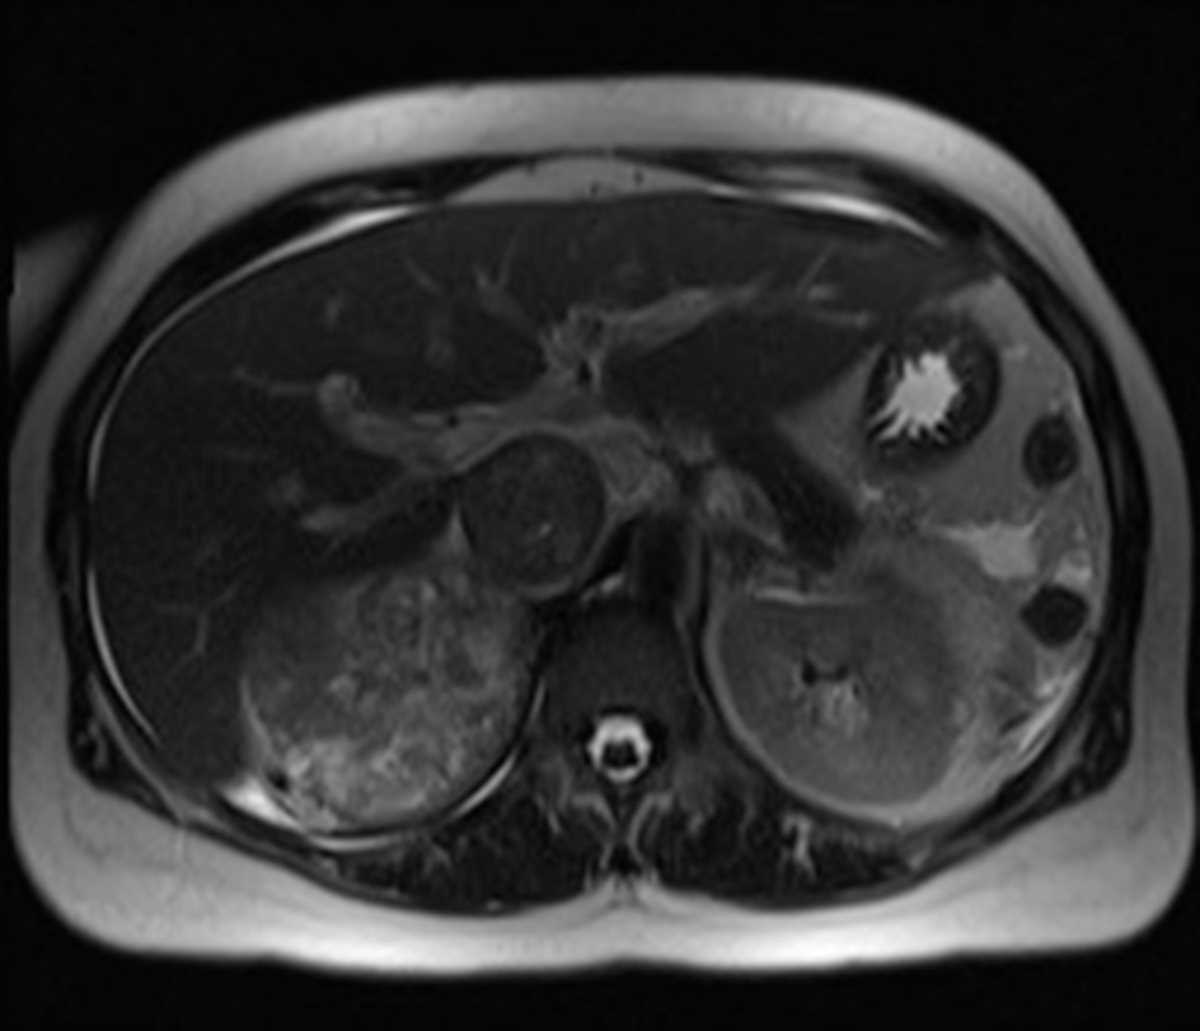

Adrenal Pheochromocytoma

Patient with hypertension. MR images demonstrate a T2 hyperintense mass arising from the right adnrela gland, with T1 hyperintensity and heterogeneous hypervascularity on the post-gadolinium images. This is the classic MR appearance of a pheochromocytoma.